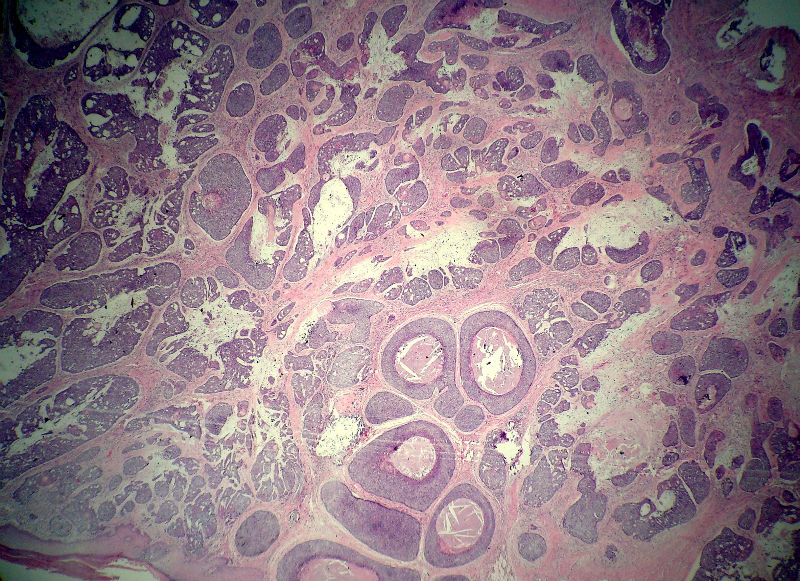

男,49岁,后枕部肿物3年,偶有破溃出血。

大体:皮肤半球形隆起,大小约2.3×2厘米,高出皮表0.8厘米,切面灰白,质地细腻。

似乎既有腺样结构,也有角化珠形成,还有细胞团内的粉刺样坏死。

大部分区域看着象基底细胞癌,后面几张(11-14)看着象是鳞癌。综合考虑基底细胞样鳞癌。